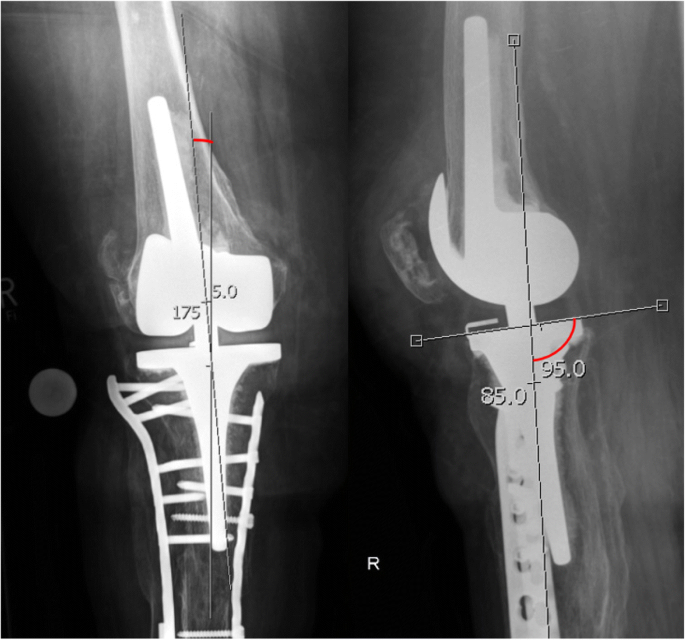

Periprosthetic Tibial Fractures In Total Knee Arthroplasty An Outcome Analysis Of A Challenging And Underreported Surgical Issue Bmc Musculoskeletal Disorders Full Text